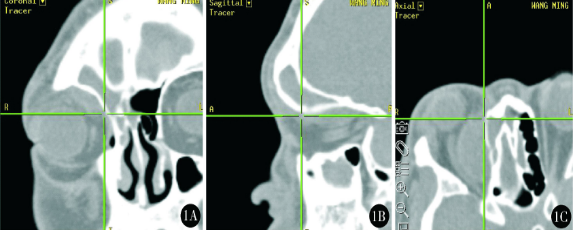

圖片顯示光學(xué)導(dǎo)航下的三維立體定位